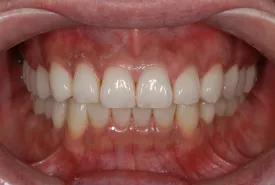

治療完了時

| 患者様のお悩み | 外傷で歯が抜けた |

|---|---|

| 治療法・使用素材 | インプラント治療の後、セラミック治療 |

| 患者様の年代 | 20代 |

| 治療開始年齢 | 20代 |

| 治療にかかった期間 | 8か月 |

| 性別 | 女性 |

| この治療のリスクについて | インプラントが正しい位置に入るかどうか |

| 治療にかかった費用 | 45万円 |